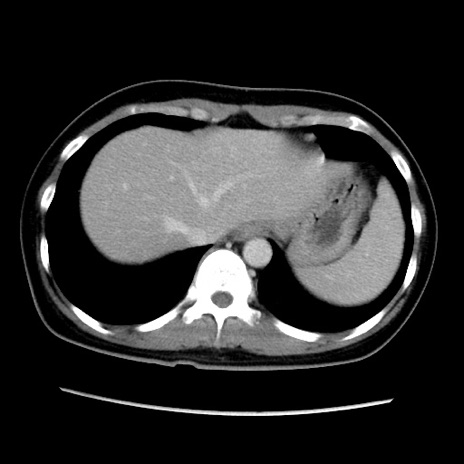

症例39(横断像)

【症例】40歳代女性

【主訴】上下腹部痛

【現病歴】2日目から下腹部痛あり。夜間は痛みで眠れなかった。昨日より上腹部痛と下痢が出現。臥位で痛みは軽快したため、休んでいた。本日になって臥位でも立位でも痛みが強くなってきたため救急要請。

【既往歴】子宮内膜症

【身体所見】部:平坦・軟、左上下腹部に圧痛あり、反跳痛あり。

【データ】WBC 21800、CRP 26.78